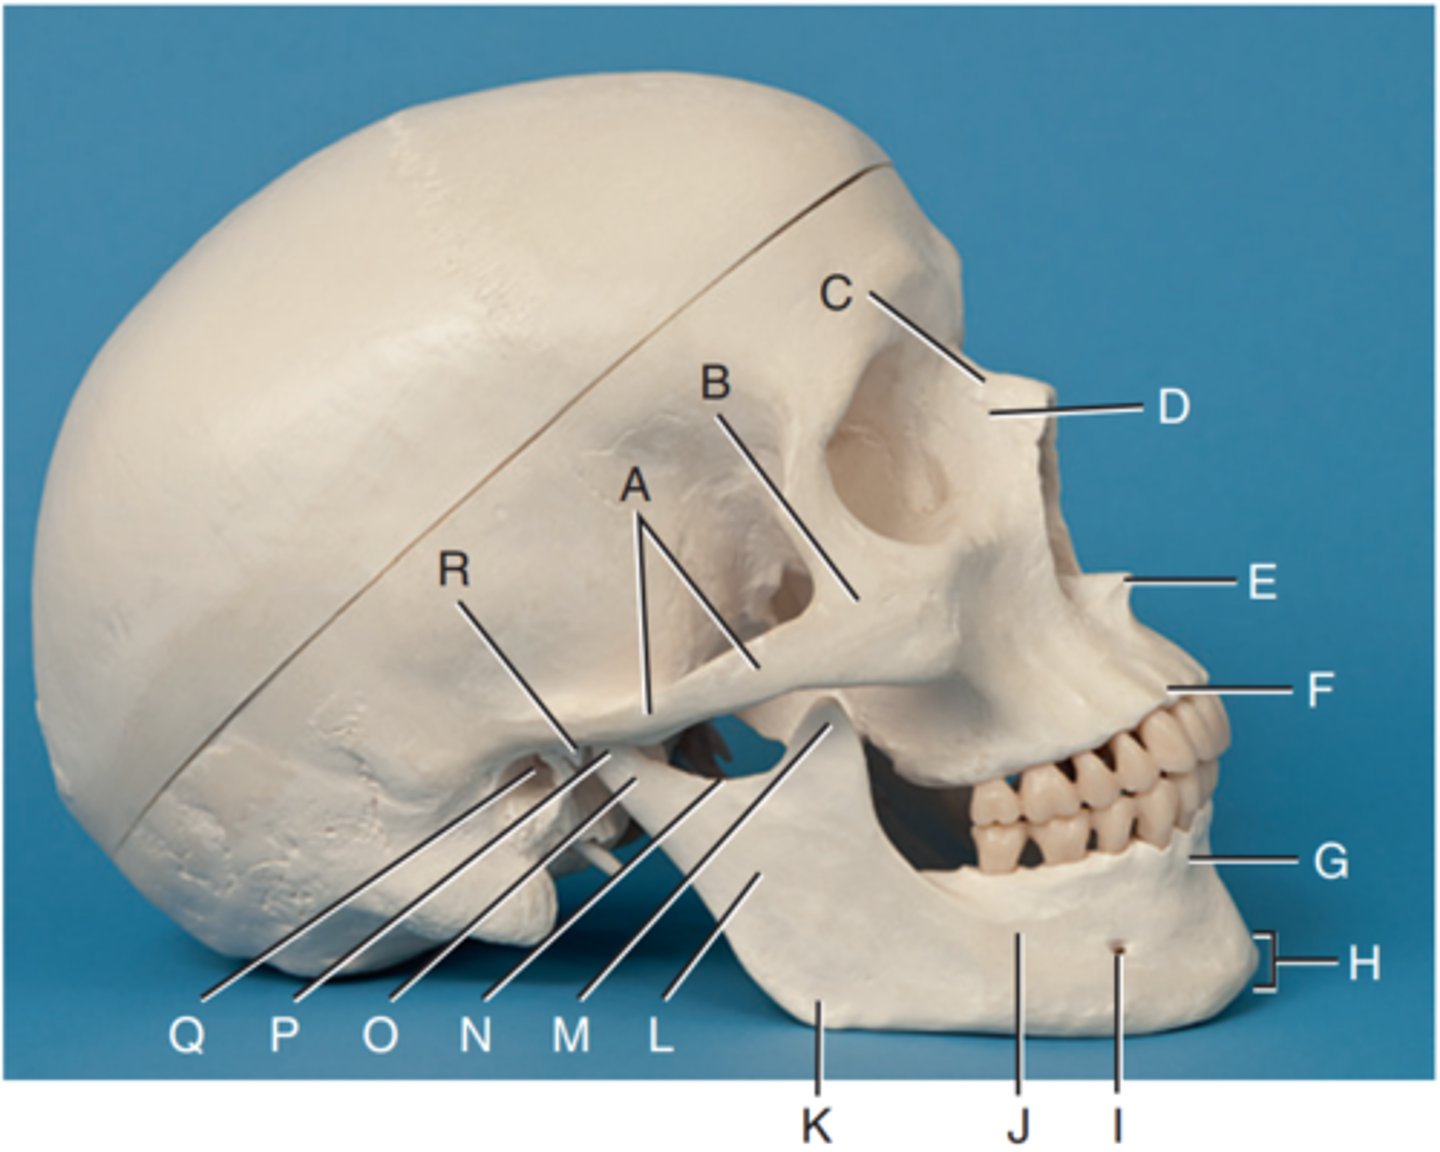

Zygomatic arch

Label A

Right zygomatic bone

Label B

Right nasal bone

Label C

Frontal process of right maxilla

Label D

Anterior nasal spine

Label E

Alveolar process of maxilla

Label F

Alveolar process of mandible

Label G

Mentum or mental protuberance

Label H

Mental foramen

Label I

Body of mandible

Label J

Angle (gonion)

Label K

Ramus of mandible

Label L

Coronoid process

Label M

Mandibular notch

Label N

Neck of mandibular condyle

Label o

Condyle or head of mandible

Label P

EAM

Label Q

TM fossa of temporal bone

Label R

Greater wings of sphenoid

Label S

Lesser wings of sphenoid with anterior clinoid processes

Label T

Ethmoid sinuses between orbits

Label U

Body of maxilla containing maxillary sunuses

Label V